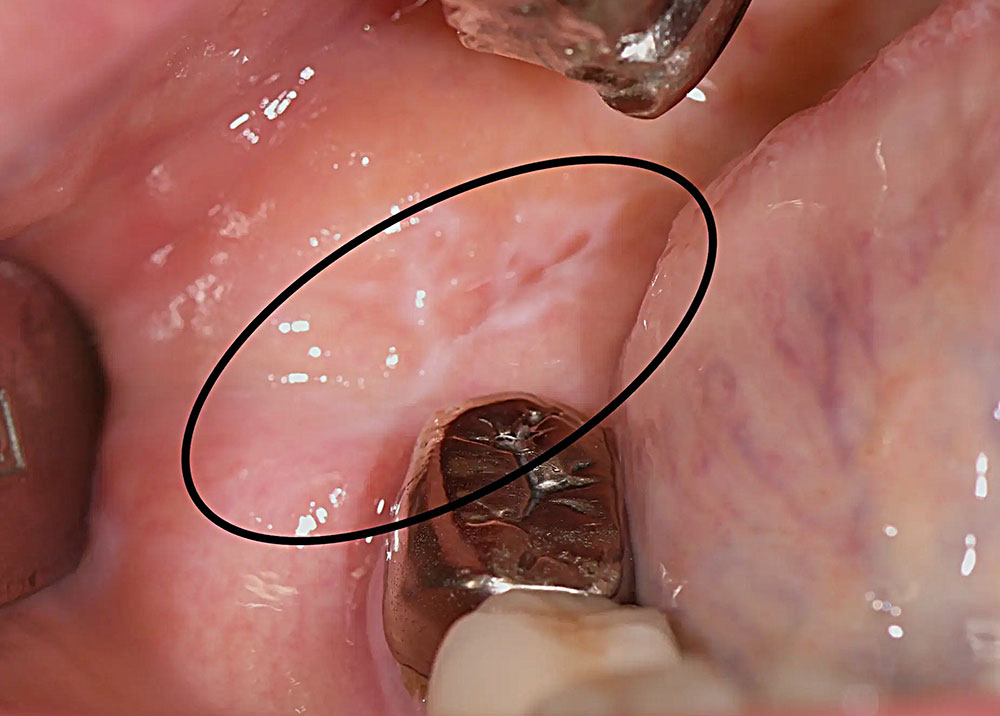

1.歯と素材の間にできる隙間

銀歯の素材は、歯と熱膨張率が大きく異なります。そのため、冷たい物や熱い物を飲食するたびに、銀歯が膨張・収縮を繰り返し、歯との間にわずかな隙間が生じてしまうのです。この隙間から虫歯菌が侵入し、再び虫歯になってしまう「二次カリエス」のリスクを高めます。

3.虫歯の発見のしにくさ

銀歯は金属の色をしているため、外から見ただけでは歯との境目やその下の状態がわかりにくいです。また、レントゲン撮影でも金属が邪魔をして、歯の中の小さな虫歯を発見しにくく、診断や治療が遅れてしまう可能性があります。